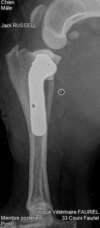

Radiographie

Des radiographies des membres, des articulations, du crâne ou de la colonne peuvent être réalisées, en particulier dans le cadre des consultations orthopédiques ou de traumatologie.